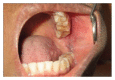

Dirofilariasis is an uncommon zoonotic parasitic infection affecting human. The natural hosts for this nematode are animals such as dogs, cats, foxes, jackals, and raccoons. This disease is endemic in South Eastern United States, Australia, Europe, and Central and Southern Asia. Dirofilaria immitis and D. repens are the common mosquito borne filarial nematodes that cause infection. Several species of mosquitos including Mansonia uniformis, M. annulifera, and Aedes aegypti are the potential vectors for this disease in Sri Lanka. Two rare cases of dirofilariasis presenting as facial and intraoral lumps are presented.